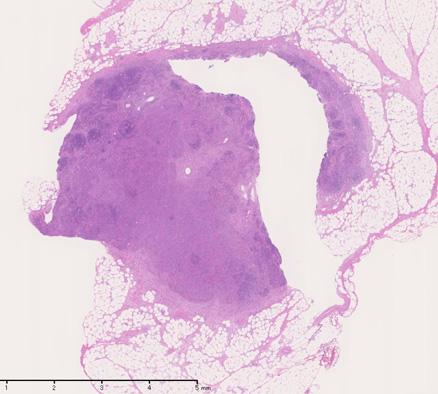

開腹リンパ節生検(腹膜脂肪組織内リンパ節, 割が入っている)

腹膜脂肪組織内から生検されたリンパ節は基本構造を失っている。低倍率のHE所見では異型細胞が不鮮明な結節構造を形成して増殖している。一次リンパ濾胞を腫瘍細胞が置換しているように見える所見がある。